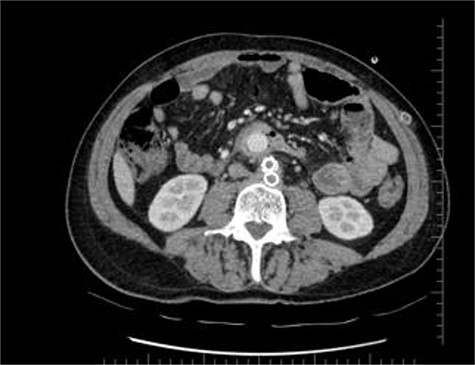

Distal CT axial section shows the two limbs of the EVAR, at the bottom. And on top of it, the Dacron straight graft part in the middle of the jejenum.

During the first days of December 2018, the patient visited another medical center because of fatigue, difficulty in breathing, lower back pain and inability to walk. His blood biochemistry revealed a very high CRP level (350 mg/dl), and complete blood count revealed a very high level of white blood cells (21 000/ul). An abdominal CT scan illustrated part of the graft was totally eroded into the small intestine (Figs 1–3). The patient was referred to my office and an infectious disease specialist. He had high body temperature (39.5°C) and was lying on the bed with lower extremities adducted to the chest. Antibiotic and supportive treatment was started. Emergency surgery was performed. We found an 8–10 cm of the straight part of the graft had become totally incorporated into the proximal part of the jejenum. The graft was freed, and 10–15 cm of the jejenum was resected and anastomosed. The area was irrigated with saline and hypochlorous acid. We then put a 20 x 10 composite mesh between the vascular graft and the intestine using a non-adhensive surface facing the intestine to prevent future graft and intestine interactions and erosion. After hemostasis, two drains were placed retroperitonally, and the abdomen was closed. On the fourth post-operative day, a high body temperature and high CRP levels were recorded. An abdominal CT revealed retroperitoneal abcess formation. During relaparotomy, the anastomosis was found to be intact, and the retroperitoneal abscess was drained and irrigated with saline. The drains were reinserted. After a month, he once again started to have high fever and high CRP levels. Again, an abdominal CT revealed abscess formation. This time, the abscess was approached transcutaneously. By making an incision in the proximal left lomber region, the abscess was drained. Another incision was made distally, and two drains were placed in the retroperitoneal area.